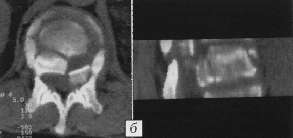

Рис. 3. Больной С. 49 лет.

а - рентгенограммы до операции; неполный взрывной нестабильный перелом

тела L1 позвонка;

б - компьютерная томограмма до операции: дислокация дорсального фрагмента

в позвоночный канал;

в - рентгенограммы через 1 год после транспедикулярного остеосинтеза Т12-L2

позвонков, коррекции деформации позвоночного канала, аутопластики и моносегментарной

эндофиксации. |

|

Рис. 4. Больной В. 24 лет.

a - рентгенограммы до операции: переломовывих Т12 позвонка, кифосколиоз;

б - компьютерная томограмма до операции;

в - рентгенограммы после задней мобилизации, устранения вывиха, коррекции

кифоза, бисегментарного спондилодеза, аутопластики, транспедикулярной

фиксации Т11-L1 позвонков. |